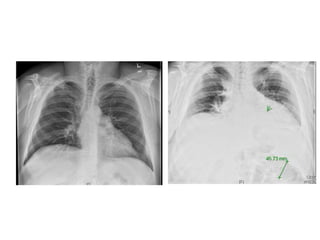

What else?

Post influenza pneumonia

Case 3 • 20yo previously healthy, one week of high fevers, chills, sweats, cough, multifocal rhonchi and rales • Influenza A positive • Treated with oseltamivir, CTX and azithromycin • No improvement in 4 days • Day 5: Persistent fevers 39.3, progressively hypoxic 2L NC to 50% FM in 24 hrs